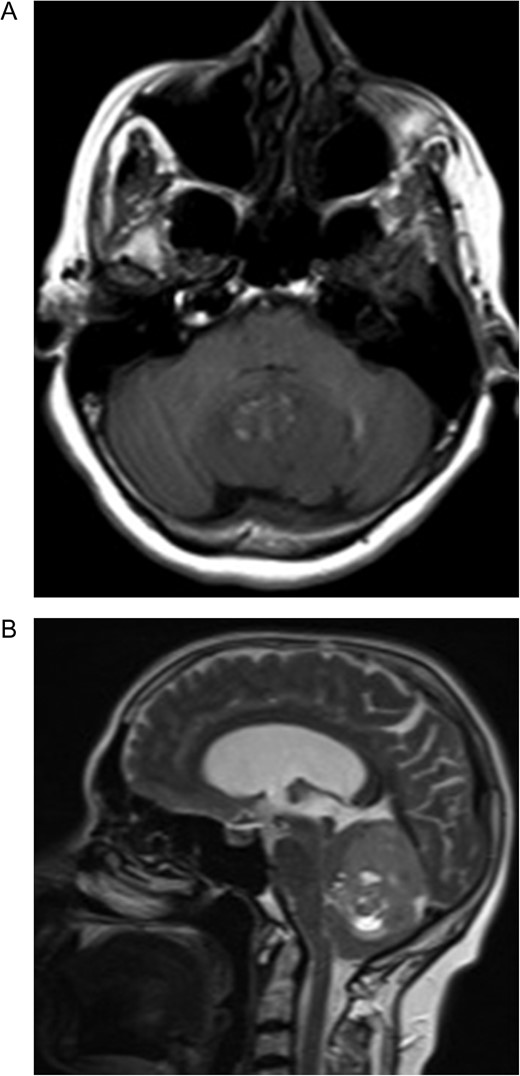

A 55-year-old woman presented with headache, dizziness and gait imbalance for 2 months. Patient’s history revealed a posterior fossa tumor that had been diagnosed 4 years ago prior to admission to our clinic. At that time, contrast enhanced of magnetic resonance imaging (MRI)showed the ill defined lesion, 5.5×3.5×4 cm in size without perilesional edema (Fig. 1A,B). During this 4 years period, her follow-up had been performed with serial MRI (Fig. 2A and B) and CT assessments (Fig. 3). Until 2 months ago, she had only intermittent headache. On neurological examination, she had cerebellar signs including ataxia and also bilateral papilledema through ocular investigations. CT assessment showed punctate calcified lesion demonstrated with undifferentiated margins of the lesion from the cerebellar parenchyma. The last MRI findings showed heterogeneous ill defined lesion without perilesional edema in vermis and extending to the adjoining cerebellar hemisphere at the supracerebellar infratentorial space with a dimension of 6.7×4×4 cm size causing compression of the fourth ventricle and marked hydrocephalous. The patient underwent surgery through a midline supracerebellar infratentorial approach in the prone position. It was a soft whitish intra-axial tumor, moderately vascular with a good plane between the vermis and cerebellum. A complete resection was achieved. The cerebrospinal fluid shunt was not decided to be placed (Fig. 4). Pathological diagnosis was reported as CLN. Immunohistochemical study, synaptophysin and neuron-specific enolase (NSE) immunopositivity were found (Fig. 5). In the mean time, glial fibrillary acidic protein (GFAP) was immunonegative and Ki-67 index was 2%. After operation, she had uneventful postoperative period and was discharged on seventh day.

(A) Post-contrast coronal T1 weighted image 4 years ago. Heterogeneous contrast enhancement of the lesion, (B) Axial-T2 weighted image showing slightly hyperintense signal of the big tumor compared with the cortex. Note that the absence of perilesional edema 4 years ago.

Preoperative MRI (A) Axial T1-weighted MRI showing hypointense lesion located in the cerebellar vermis. Note the hyperintense area corresponding to the fat component. (B) The lesion is hyperintense and well circumscribed on sagittal T2-weighted MRI. Note the supratentorial hydrocephalus secondary to compression of the fourth ventricule.